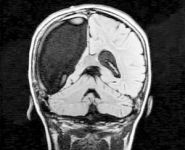

9-летняя жительница Бостона по имени Кэмерон поставила в тупик врачей и ученых. Всего за несколько недель, девочка смогла прийти в себя после сложнейшей операции по удалению правого полушария головного мозга.

Как сообщает eg.ru, начиная с трех лет Кэмерон, страдала тяжелой болезнью - синдромом Расмуссена или проще говоря, очаговым энцефалитом. Это коварная болезнь неизвестного происхождения начинается в детском возрасте и поражает только одно полушарие головного мозга, разрушая там нервные клетки.

В течение долгого времени малышку мучили судороги и тяжелые, едва ли не ежедневные, приступы эпилепсии. В конце концов, врачи вынуждены были удалить ребенку правое полушарие, которое отвечает за чувства, эмоции и ориентацию в пространстве.